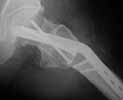

A male 56 years old was operated in Aug 2003 - valgus osteotomy performed because of delayed admission with neck fracture (2 months) images 1,2. Smoker, no other major medical problem.

Image 1